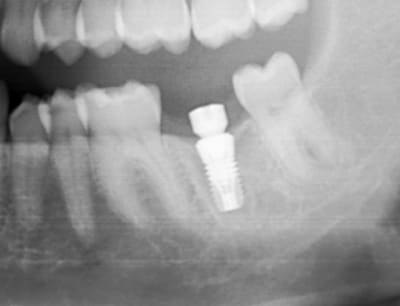

bon les pièces jointes d'alhoun.

décidément aussi nul en endo qu'en internet, et ton implant il est de traviole;)

Ok j'ai compris. Par contre, sur la radio l'implant a l'air d'être conique sur toute sa hauteur, c'est une illusion d'optique où il est vraiment comme ça, je ne le vois pas sur le site d'Astra ?

tu parles de celui de growler?

c'est normal c'est pas un astra, c'est un easy implant, mais il est pas conique tout le long il me semble.

çà doit être une déformation du cliché, regardes bien le premier cliché avec le pilier de cicatisation: on voit bien la partie cylindrique puis l'évasement.